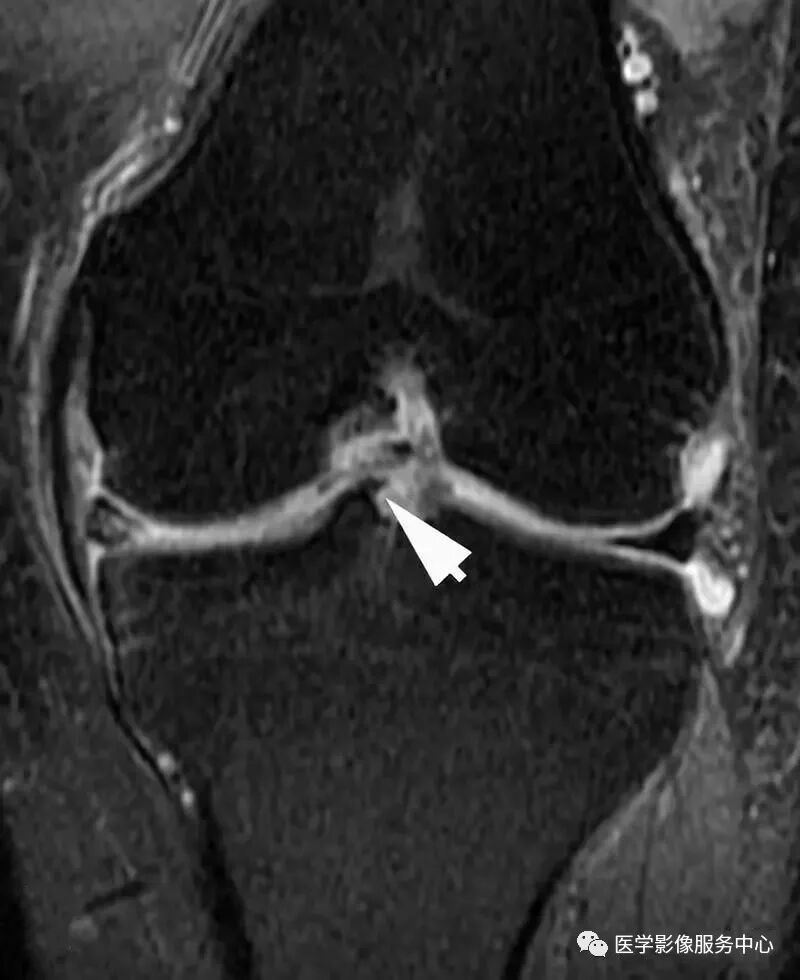

白色箭头所标记为膝横韧带

白色箭头所指为横韧带,黑色箭头所指为内侧半月板前角,位于横韧带正后方

白色箭头所指为横韧带,外侧半月板前角位于横韧带后方

膝横韧带经常容易被误诊为半月板前角撕裂或损伤,我们需要知道有这根韧带,而且要知道它特殊的解剖位置和半月板的形态是否正常,从而与半月板前角鉴别;